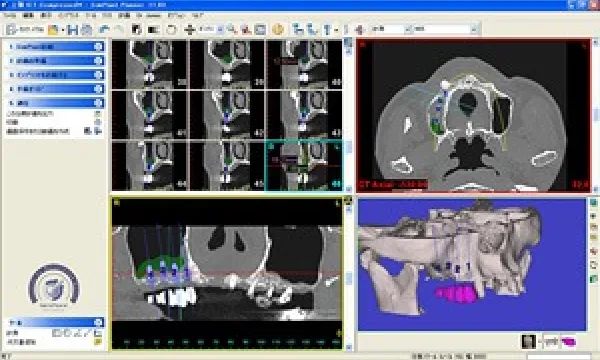

1.診査

インプラントで一番大切なのが診査であると思います。当院では通常のレントゲン撮影にくわえほぼ100%の患者さまに、 CT撮影を行っています。またそのデータを変換して、インプラントシミュレーションソフトのシンプラント上でインプラント埋入 シミュレーションを行っています。 これにより、骨の厚みや量の過不足にくわえ骨の密度や質までも正確に把握することが可能になり、より安全確実な インプラント埋入が可能になります。 最近は歯科用コーンビームCTを完備した医院もありますが、当院が医科用CTにこだわって撮影をお願いしている 第一の理由は、歯科用CTでは骨の質や密度を反映するCT値が出ないところにあります。 当院ではCT撮影専用の医院であるメディカルスキャニングセンターと提携して速やかな撮影が可能です。

インプラント埋入シミュレーション

2.診断

シンプラント上でシミュレーションしたうえで、年齢、骨の量、質、厚み等勘案しインプラントの治療計画を提案いたします。 症例によってはそのまま、場合によっては不足している部分に骨を作ってからインプラントの埋入を行うことになります。